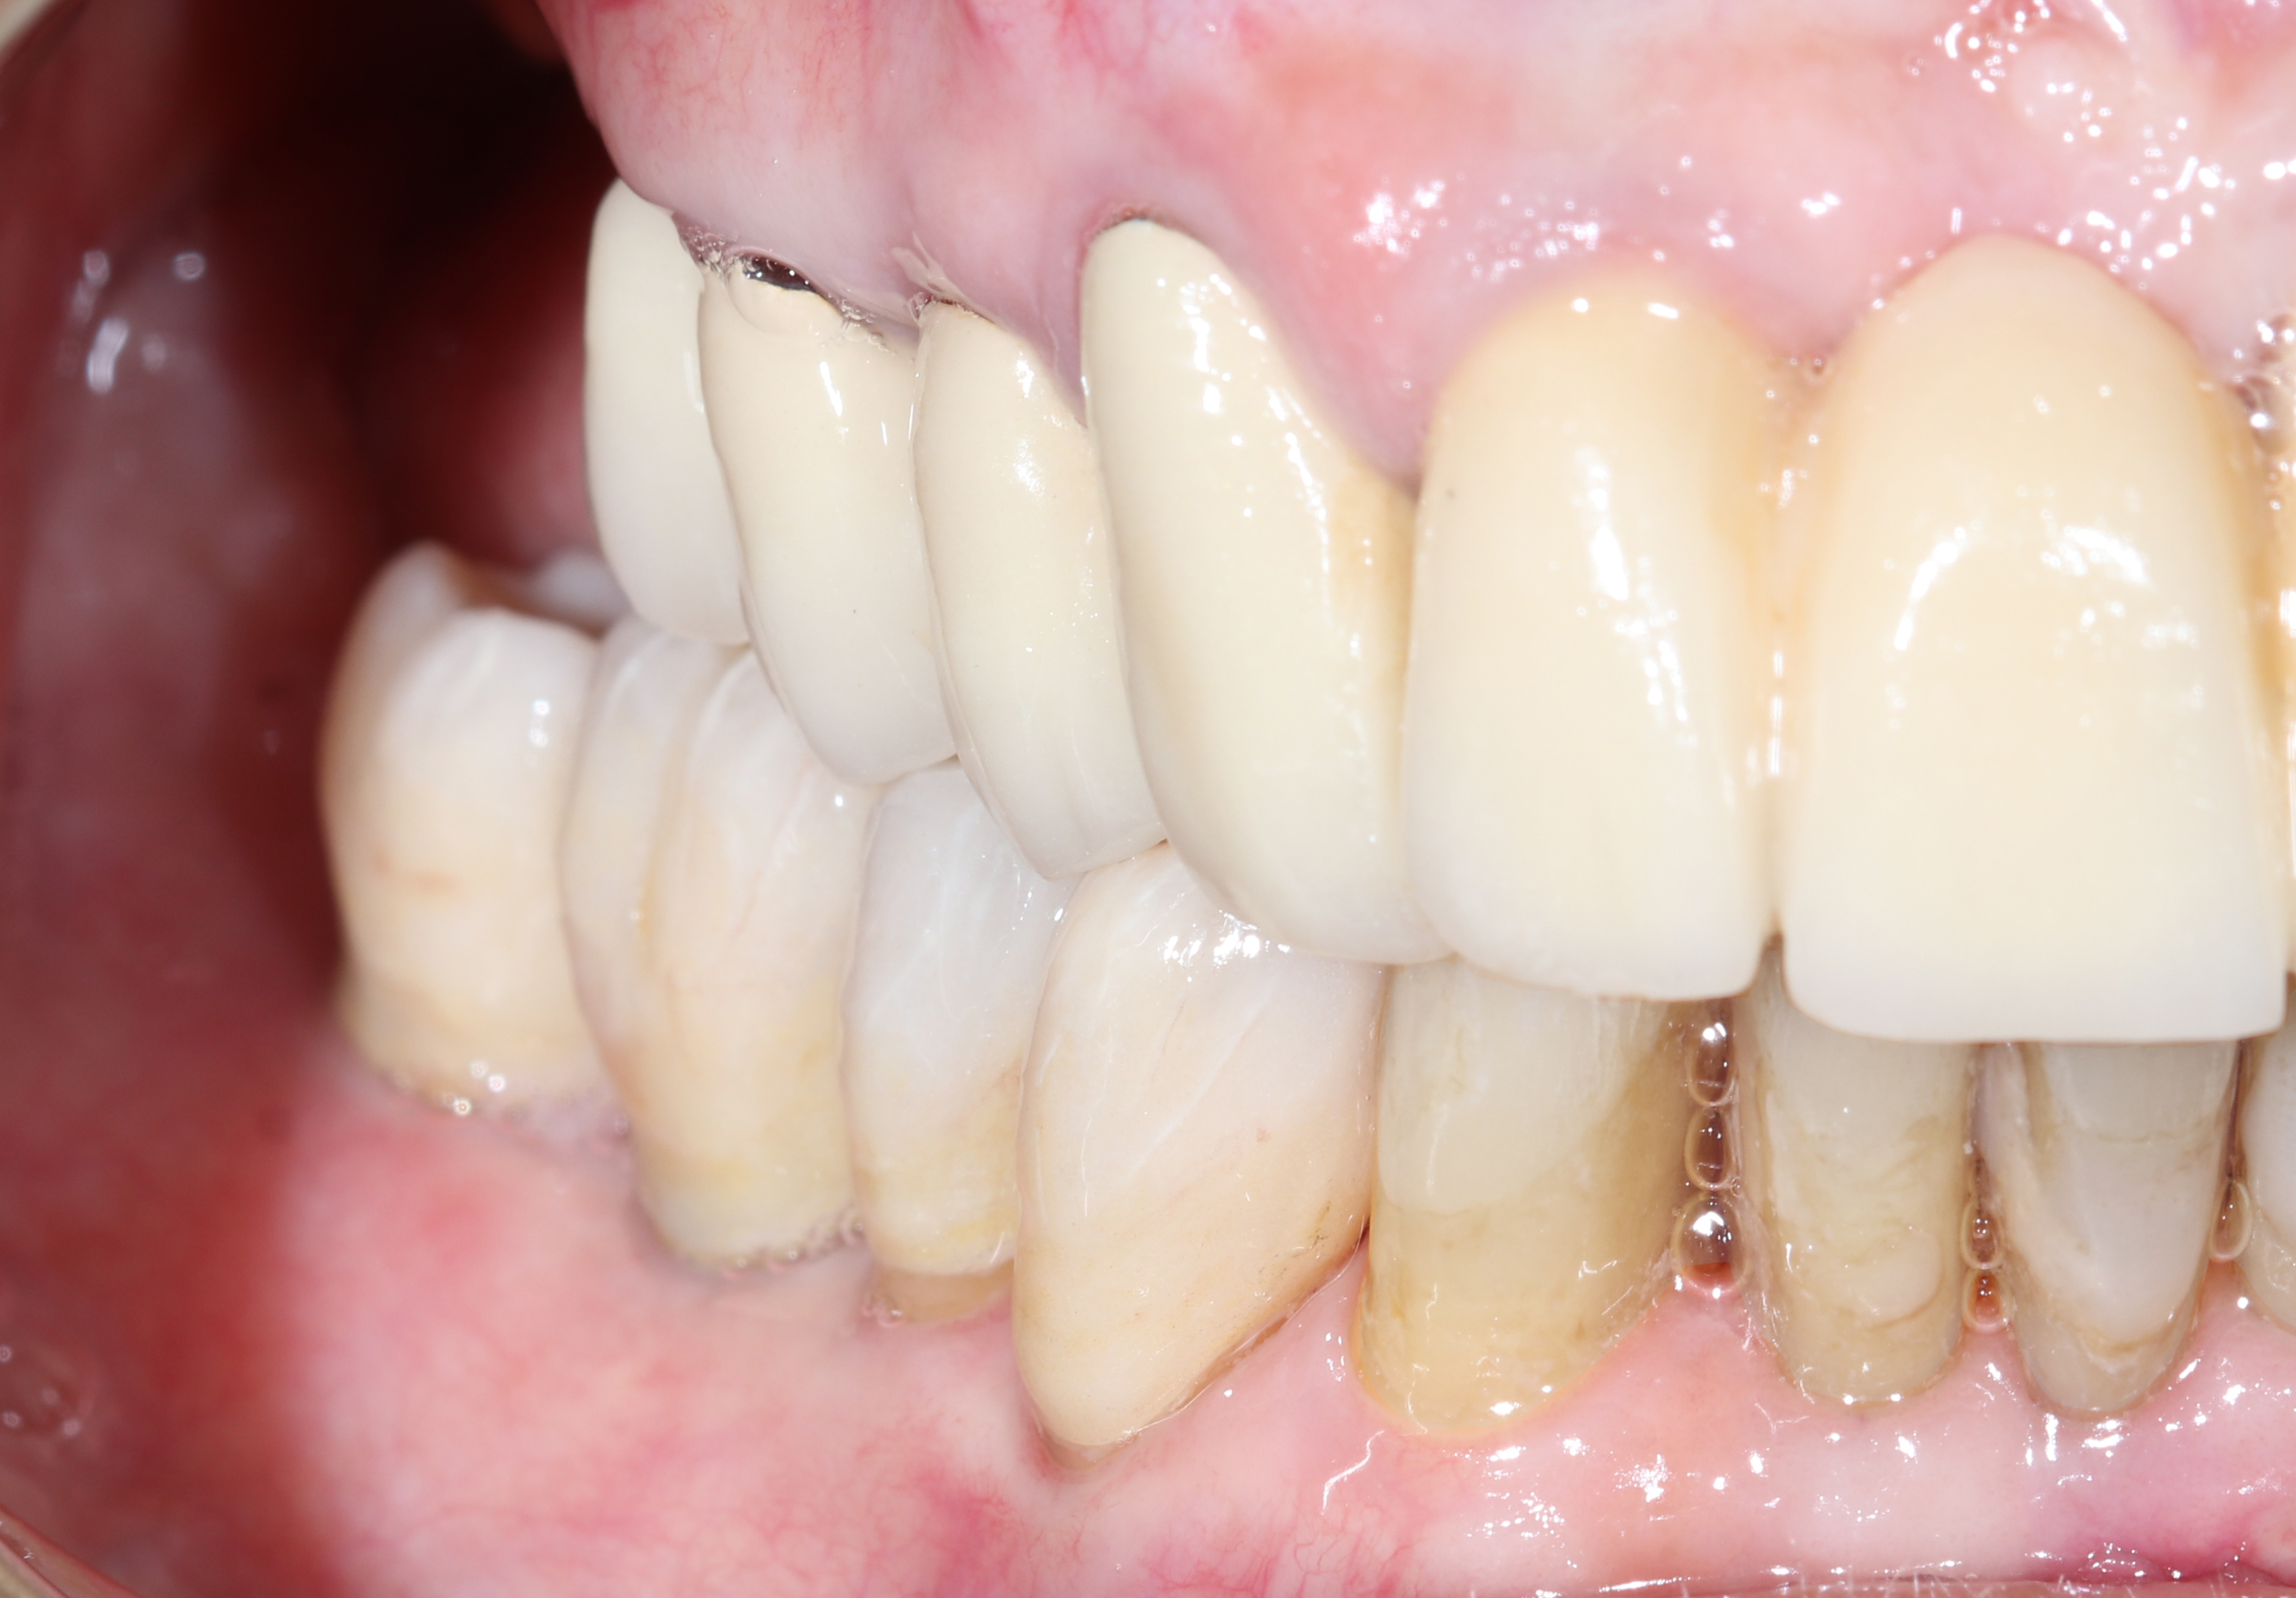

Τελική προσθετική αποκατάσταση

Μετά την επιτυχή οστεοενσωμάτωση, προχωρήσαμε σε ψηφιακή αποτύπωση με ενδοστοματικό σαρωτή και στην κατασκευή:

• Ακίνητης ολοκεραμικής γέφυρας ζιρκονίου δύο τεμαχίων επάνω στα εμφυτεύματα

• Δύο στεφανών ζιρκονίου στους παρακείμενους προγομφίους

Η τελική αποκατάσταση προσέφερε φυσική αισθητική, σταθερότητα και αποκατάσταση πλήρους μασητικής λειτουργίας, βελτιώνοντας ουσιαστικά την ποιότητα ζωής της ασθενούς.